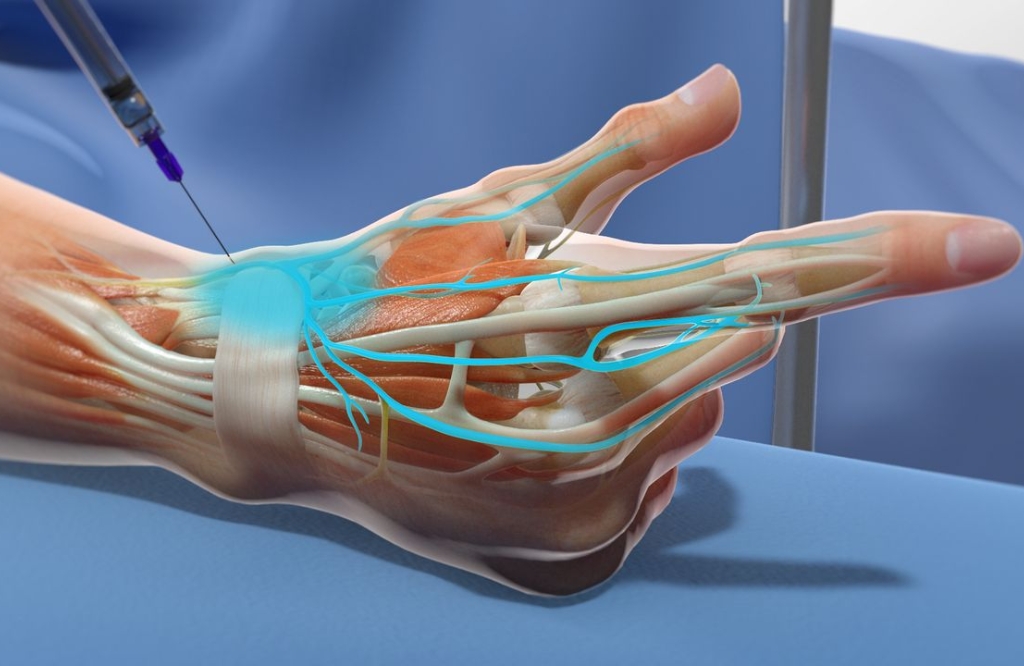

O bloqueio de nervo é um procedimento minimamente invasivo utilizado para o alívio rápido e eficaz da dor crônica. A técnica consiste na aplicação de anestésicos e anti-inflamatórios diretamente nos nervos responsáveis pela dor, reduzindo a sensibilidade da região afetada e proporcionando mais conforto ao paciente.

Essa abordagem é especialmente indicada para pacientes que sofrem com dores na coluna, hérnias de disco, neuralgias, síndrome do túnel do carpo e dores articulares crônicas, condições que comprometem a mobilidade e impactam a qualidade de vida. Com esse tratamento, é possível reduzir o uso de analgésicos, evitar procedimentos cirúrgicos e restaurar o bem-estar.

Os bloqueios são personalizados conforme a necessidade de cada paciente e podem ser utilizados como alternativa para evitar cirurgias ou como parte de um tratamento multidisciplinar. Além disso, os efeitos podem ser duradouros, permitindo um retorno mais rápido às atividades normais.